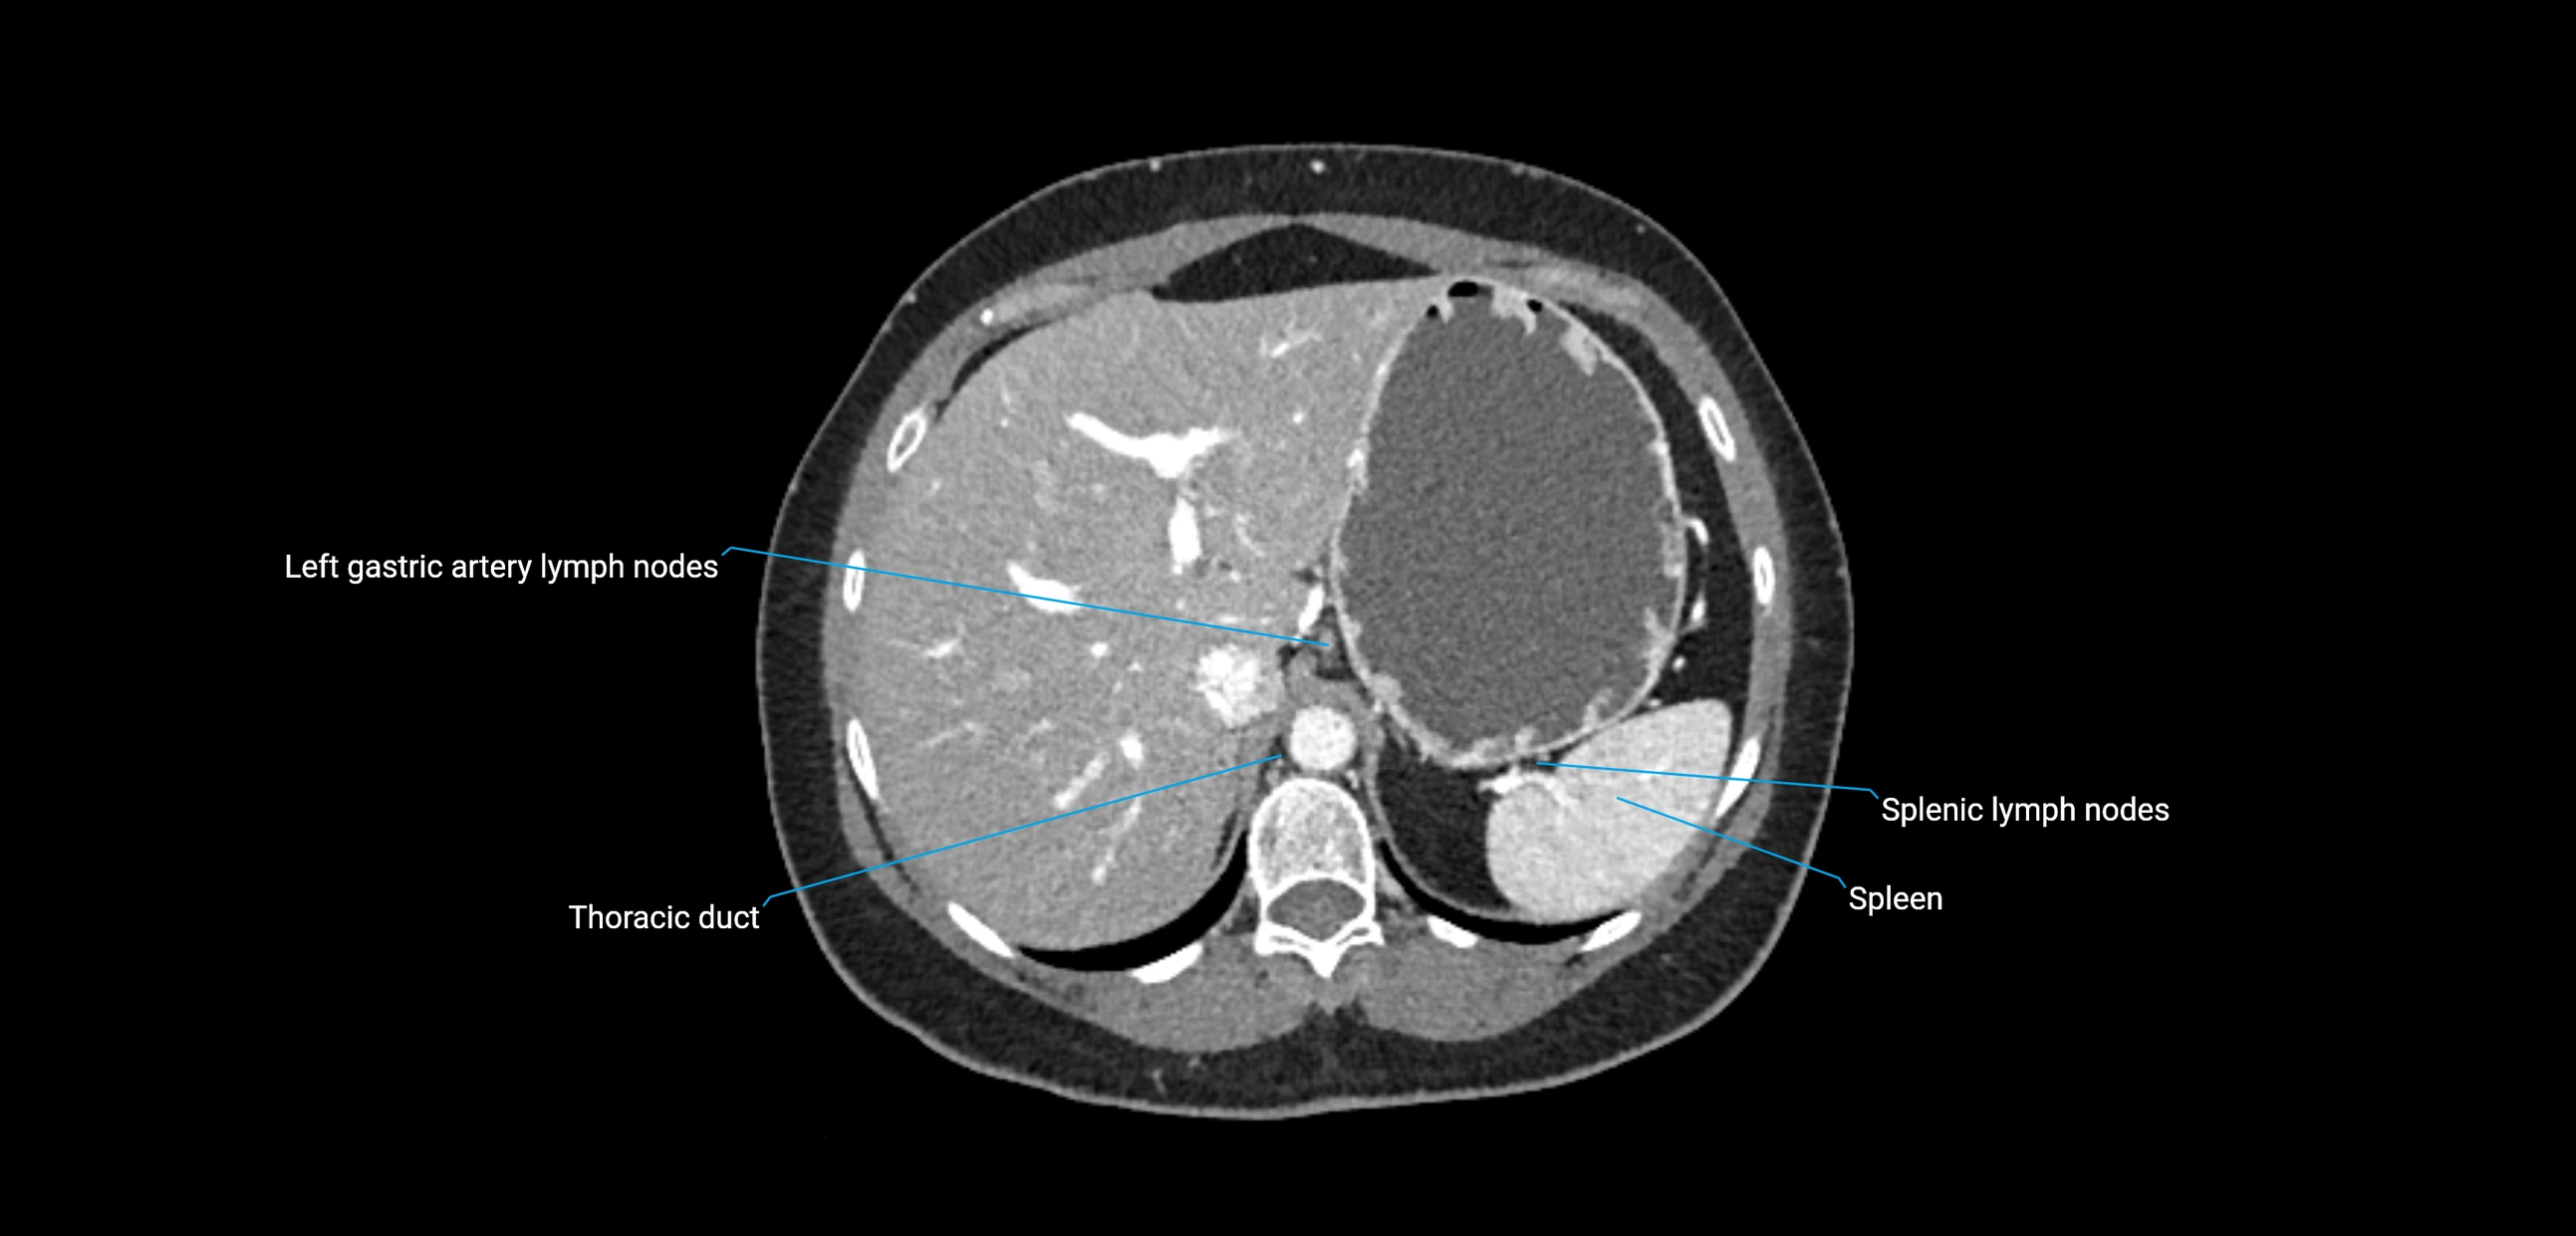

CT Appearance

CT Pre-Contrast:

• Nodes appear as soft-tissue density nodules adjacent to the aorta and IVC

• Calcification may be seen in chronic infections (e.g., tuberculosis)

CT Post-Contrast:

• Normal nodes enhance homogeneously

• Malignant nodes may show heterogeneous enhancement, central necrosis, or conglomerate formation

• Size >1 cm short axis is suspicious, though morphology and distribution are equally important